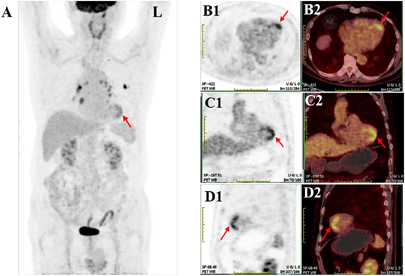

为进一步明确病变性质及全身情况,行18F-FDG PET/CT全身显像(图1A),见左室前壁近心尖、心尖部、间壁近心尖及下壁近心尖局灶性异常摄取,最大标准摄取值(SUVmax)5.0,符合LAD支配区域,疑伴CAD。CTA示:LAD多发钙化、非钙化斑块,管腔明显狭窄,最狭窄处约68%(图3A);左回旋支(LCX)及右冠状动脉(RCA)管壁多发钙化,管腔不明显狭窄。追问病史了解到患者近2年来反复出现活动后胸闷不适,位于心前区,休息数分钟后即缓解,未予重视。遂行运动负荷及静息MPI(图2)示左室前壁近心尖、心尖部、下壁近心尖及间壁近心尖(LAD供血区域)重度可逆性心肌缺血。后行CAG:LM:未见明显狭窄。LAD:近中段90%狭窄,远端血流TIMI0~1级。LCX:近段斑块浸润30%狭窄,远段50%狭窄。RCA:全程斑块浸润,近中段及中远段50%狭窄。综上,临床考虑为LAD严重狭窄至心肌缺血,诊断为CAD。

肿瘤患者在禁食条件下行18F-FDGPET/CT检查时,会遇到心脏局灶性18F-FDG摄取,摄取部位以左心室最常见,心肌缺血是病因之一[1]。心肌缺血后,局部心肌葡萄糖代谢异常(摄取增加)可持续一段时间,称作"缺血记忆"[3]。肿瘤患者18F-FDG PET/CT显像前需禁食4~6 h以上,以抑制正常心肌对葡萄糖的生理性摄取,可一定程度反映心肌缺血、心脏炎症对葡萄糖的病理性摄取[4,5]。Dou等[6]报道,86%的不稳定型心绞痛患者出现"局灶性"或"弥漫性"摄取。据前报道,左室心肌18F-FDG摄取主要分为如下模式:1.无摄取;2.弥漫性摄取;3.局灶性摄取;4.弥漫并局灶性摄取。存在模式3或4则定义为异常(心肌缺血),但左室基底节的局灶性或弥漫并局灶性摄取(包括乳头肌)定义为正常[6,7]。虽然心肌18F-FDG摄取存在多样性,但基于对其常见摄取模式的认识和判读,将有助于识别额外的潜在疾病。

Aikawa等[8]报道一例左小腿恶性黑色素瘤的女性行18F-FDG PET/CT检查发现左室前壁局灶性摄取,CAG证实LAD存在严重狭窄,表明无症状性CAD伴心肌缺血;随访发现左室前壁心肌局灶性摄取在成功的PCI治疗5月后消失。本例患者平时有活动后胸闷不适症状,且合并高血压、高血脂等CAD的危险因素。CTA提示冠脉三支血管多发钙化,冠脉钙化积分越高患者CAD风险等级越大[9],故该例提示CAD的高可能性。但由于受冠脉钙化伪影的干扰,CTA在评估严重性钙化时估计冠脉狭窄程度存在局限性,故本例CTA软件测量的LAD狭窄程度最重处仅68%。核素负荷-静息MPI是目前临床应用广泛的无创性评价心肌缺血的影像技术,灵敏度和特异性均较高[10]。该例患者静息+负荷MPI结果证实与18F-FDG PET/CT全身显像左室心肌局灶性摄取相对应的心肌缺血,进一步验证该例患者心肌18F-FDG局灶性摄取提示CAD心肌缺血。